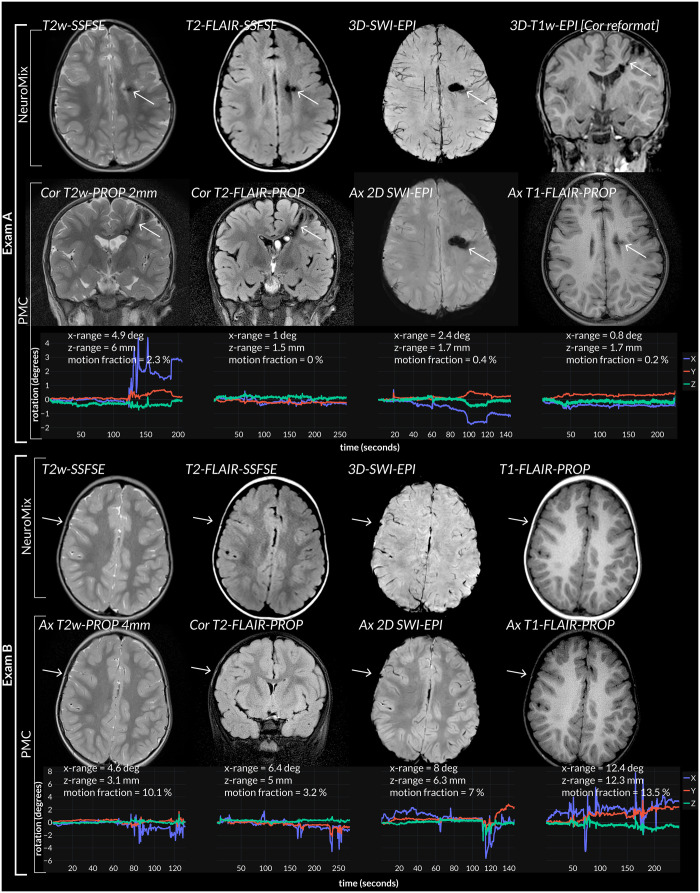

Materials and methods: Participants were prospectively recruited and investigated using an in-house developed multi-sequence scan called NeuroMix that produces T1-weighted, T2-weighted, T2*-weighted, T2-FLAIR, and diffusion-weighted images in under 3 minutes. Additionally, a self-created motion tracking device was attached to participants' foreheads to perform prospective motion correction (PMC) on 2D single-shot sequences that produce higher resolution images of the same contrasts as NeuroMix.Three neuroradiologists scored the completed series for artifacts. The effects of age group (<5 vs ≥5 years) and sequence type (NeuroMix vs PMC) were evaluated with a Chi2-test.

Results: Of the 64 participants recruited (mean age 6.7 years [2.7 standard deviation]) 58 completed their examination. Head motion recorded during PMC sequences revealed prevalent superior-inferior displacements [25% (67/293) exceeding 13.2 mm], and chin-up/down rotations [25% (67/293) exceeding 13.7°]. Sequence redundancy through NeuroMix and PMC scans resulted in 93% (54/58) of completed examinations having all series essential for producing an MRI-report rated as artifact-free, and therefore a report of high confidence in 84% (54/64) of participants. 22% (13/58) of completed exam reports could have been written using NeuroMix alone, the remaining required PMC- T2-weighted or T2-FLAIR sequences.